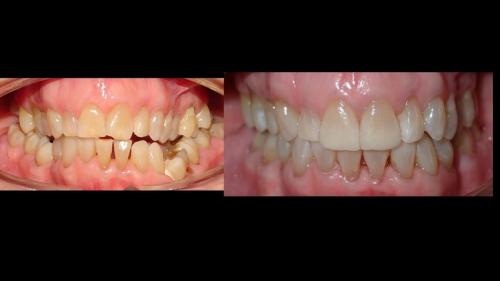

Galería de Sonrisas

large-Resultados con balance